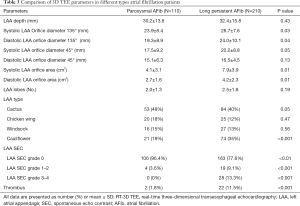

The LAA (Figure 2A,B,C,D, red arrowhead) can be seen in varying sizes during the different phases of the cardiac cycle (the yellow arrow points to the time frame of the cycle). As demonstrated in Figure 2, patients with long-standing AFib showed a different contraction and relaxation LAA morphology during AFib, noting that a coumadin ridge was found in the same patient (Figure 2, asterisk). LAA morphology parameters, including depth, orifice diameter, and orifice area should be strictly assessed in the same cardiac cycle. In order to discover more LAA details and differences between the two AFib classifications, these LAA morphology parameters were further collected and compared by RT-3D TEE. We found that the LAA orifice was markedly enlarged in long-standing patients, compared with paroxysmal AFib group (Figure 3, Table 3). The diameter of the LAA orifice was carefully measured from multiple angles, including the 45° and 135° views. The average systolic inner diameter of the LAA opening in the 135° view were 23.9±8.4 and 28.7±7.6 mm, in the paroxysmal and long-standing groups, respectively (P=0.03). The average diastolic inner diameter of the LAA opening in the 135° view were 19.3±8.9 and 24.0±10.1 mm in paroxysmal and long-standing groups, respectively (P=0.04). Meanwhile, there was no difference in terms of the LAA orifice diameter in the 45° view (P=0.05 in systole, P=0.13 in diastole). Long-standing AFib group patients also had a markedly greater value of LAA area in the systolic and diastolic phases compared with the paroxysmal group (P=0.01). However, the LAA depth did not differ significantly between them (30.2±13.6 vs. 32.4±15.8, respectively, P=0.43) (Table 3).

LAA lobes and morphology typing in AFib patients

We also used RT-3D TEE as a tool to determine the number of LAA lobes, and to identify the relationship between the number of lobes and the AFib types. We found that the majority of LAAs had between two and three lobes, while one lobe accounted for a relatively small proportion in our cohort study (Table 3). Also, we identified a trend of long-standing AFib patients having more LAA lobes compared to paroxysmal group patients, however no statistical difference was found (P=0.19). In the paroxysmal AFib group, the LAA morphology typing were ordered as follows: cactus type (46%), cauliflower type (19%), chicken wing type (20%), and windsock type (15%), compared to cactus type (40%), cauliflower type (32%), chicken wing type (16%), and windsock type (12%) in the long-standing group (Table 3, Figure 4). The percentage of cauliflower type LAAs in the long-standing AFib group increased significantly (P<0.001), whereas the proportion of non-cauliflower type LAAs decreased slightly, compared with the paroxysmal AFib group (P≥0.05).

SEC, thrombus and relationship with LAA morphological typing in AFib patients

RT-3D TEE could detect LAA SEC and sludge visually. We defined four grades according to the severity SEC by 3D TEE. Four (3.6%) patients in the paroxysmal AFib group had mild SEC; no severe SEC was detected in these patients. However, there were 28 (13.3%) patients with LAA SEC grades 3–4, and 19 (9.1%) patients with LAA SEC grades 1–2 in the long-standing AFib group, and the differences were statistically significant (P<0.001). With regards to LAA thrombus clot, we evaluated the 2D TEE and 3D TEE in the LAA long axis view, and 3D TEE in the superior view into LAA, in all patients (Figure 5). Most paroxysmal AFib patients had normal LAA morphology and no SEC or thrombi (Figure 5A,B,C). SEC was definitely more likely to occur in the long-standing AFib patients (Figure 5D,E,F,G,H,I). In addition, the long-standing AFib group had a much higher thrombus occurrence rate, and thrombi were found in 22 (11.5%) patients compared with 2 (1.8%) in the paroxysmal AFib group (P<0.001). Moreover, with regard to diagnosis rate, 2D TEE mistook the acoustic artifact from crest (used for lobulation) as SEC, and even thrombus, in some cases (Figure 5J,K,L). The uncertainty of thrombi detection was significantly decreased by 3D TEE compared with 2D TEE (P<0.001), and the certainty of thrombi detection by 3D TEE also decreased slightly (P=0.06). In our study cohort, the rate of thrombi and prior stroke/TIA was not very high [24 (7.5%) and 29 (9.1%), respectively in the overall study population]. However, in most cases in our research, thrombi were more likely to occur in cauliflower type LAAs [odds ratio (OR) 2.1, 95% confidence interval (CI): 1.1–8.5, P=0.031].